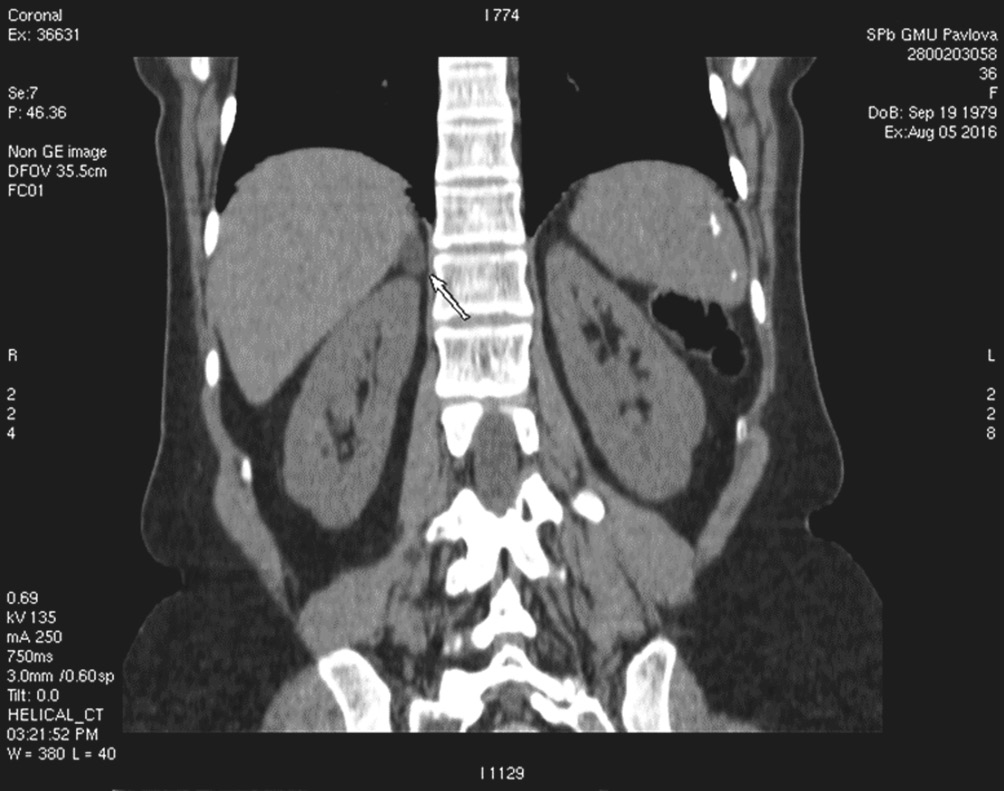

Для оценки состояния надпочечников, а также для дифференциальной диагностики различных форм ПГА 05.08.2016 пациентке была выполнена компьютерная томография органов брюшной полости и забрюшинного пространства с контрастированием (контраст вводился перорально и внутривенно). Было выявлено образование в медиальной ножке правого надпочечника (см. рисунок).

Компьютерно-томографическая картина аденомы правого надпочечника. Образование указано стрелкой